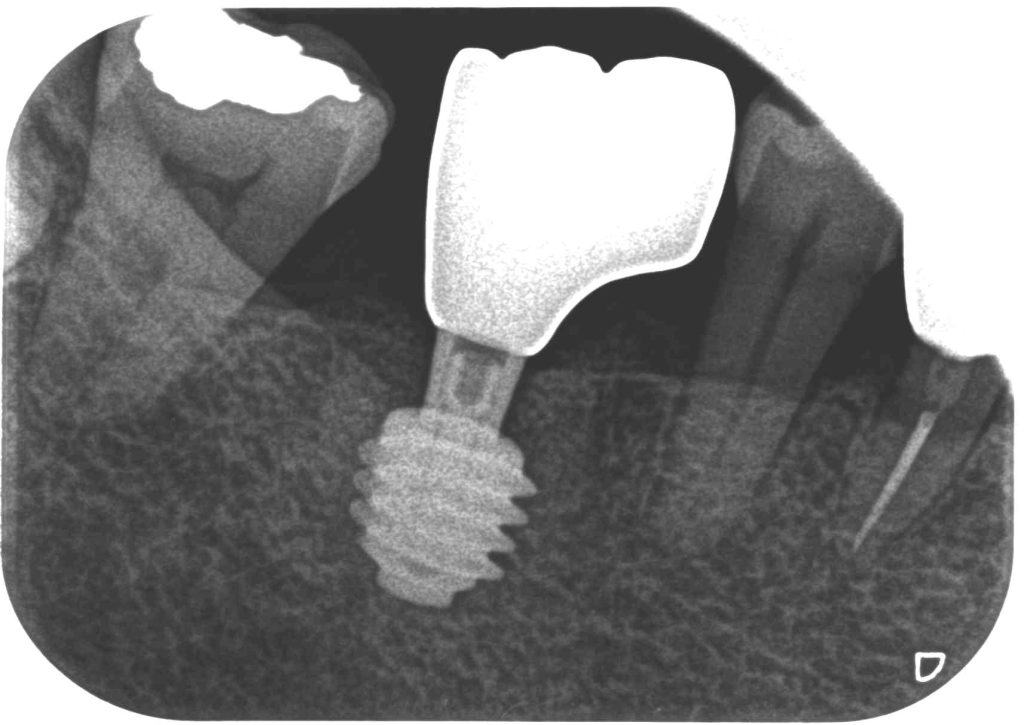

症例450代 男性 主訴 噛めるように歯を入れて欲しい

治療前

治療後

入れ歯の選択肢になく、ブリッジは健全な歯を削って被せることから、力学的に強く、両隣在歯を守るインプラントを選択。右上6番にインプラントを埋入。

オペ後、骨との密着値も良く、約2ヶ月後には、ジルコニアを装着し終了。

リスクとしては外科的侵襲がある。デメリットは、保険外診療の為、経済的負担がある。

費用 53万(税込)(オペ・仮歯・最終補綴物まで含む)